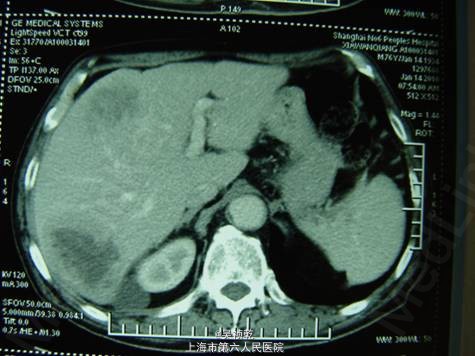

术前诊断:直肠癌伴肝肺转移(肝脏多发,肺单发) 行直肠癌TME手术:术中探查:肝脏多发转移结节,最大者4cm, 无腹水及腹盆腔种植结节; 直肠肿瘤距肛门8cm,侵犯浆膜外脂肪组织。 病理:溃疡型管状腺癌II级,4.5*3.5*2cm,侵至肠壁全层,达肠周脂肪组织,肠周淋巴结转移: 6/12,肠系膜动脉根部0/2淋巴管(+)神经周围(+)血管(+)。K-ras检测:野生型 术后行化疗方案为:FOLFOX 4+Cetuximab (q2wk * 6次) 后评估肿瘤部分缓解,6次化疗结束后改为XELOX / q3wk*6次,评估肿瘤无进展。 下图可见复查的影响学资料相比化疗前肿瘤有明显缩小。

患者目前术后8个月,经手术及术后化疗+靶向治疗后肿瘤无明显进展,由此带来了我们的疑问,目前摆在我们面前的治疗方案有: 1.继续XELOX+西妥昔单抗治疗。 2.手术切除肝转移或肺转移病灶 3.射频治疗 4.更换其他化疗方案 请大家讨论一下下一步治疗方案,谢谢。